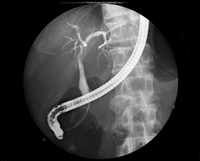

業務内容は胃がん検診が最も多く、その他にも大腸透視や脊髄造影、ERCP(内視鏡的逆行性胆管膵管造影)、イレウス管挿入、整復や気管支鏡生検など多岐に渡ります。